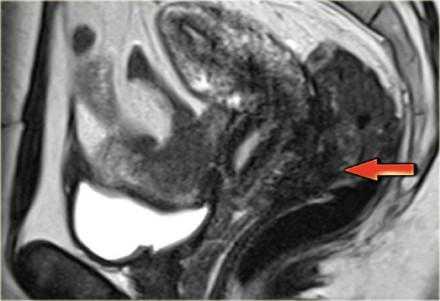

На Т2 взвешенных МР-томограммах определяются признаки эндометриоза с поражением стенки мочевого пузыря

На сагиттальных Т2 взвешенных МР-томограммах определяется поражение стенки мочевого пузыря на всю ее толщину, обусловленное эндометриозом, дающей изоинтенсивный сигнал по сравнению с мышцами; видны также гиперинтенсивные очаги, сопоставимые с расширенными эндометриальными железами. На Т1 взвешенной МР-томограмме с жироподавлением в зоне кровоизлияния визуализируются множественные мелкие кисты, дающие гиперинтенсивный сигнал